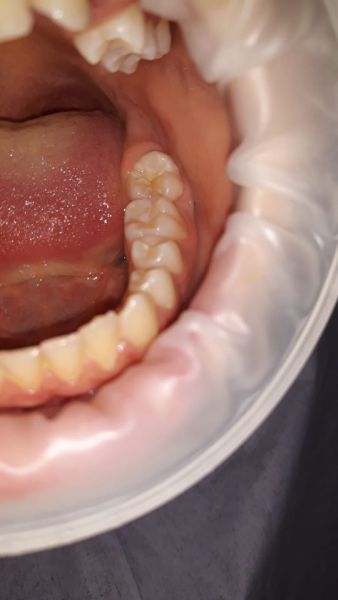

Le sigillature dei solchi e delle fessure sono otturazioni meccaniche che vengono effettuate per correggere le anomalie dello smalto dentario presenti nelle superfici masticatorie dei molari, dei premolari e, in alcuni casi, sulla superficie palatale dei denti anteriori impedendo alla placca batterica di penetrarvi dentro.

Perchè i bambini, solitamente, non riescono a spazzolare bene, soprattutto, i molari ed i premolari e nei solchi e nelle fessure si possono depositare residui di cibo e batteri che favoriscono la formazione di carie.